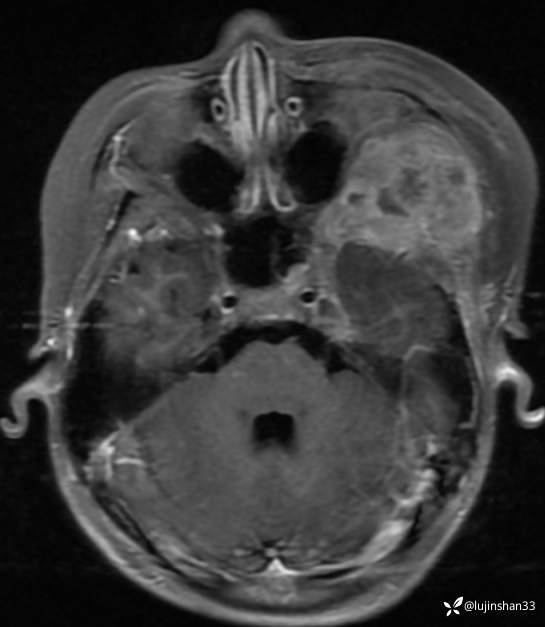

简要病史:患儿父母半年前发现患儿左颞部较右侧突起,无伴随症状,未重视未诊治,1月前,患儿左颞部肿物长大,伴头晕,向一侧倾倒感,头痛,两次剧痛,余为胀痛,偶有夜间出现左下颌区域皮肤麻木,咀嚼时左面部疼痛,10天前,患儿出现左眼睑肿胀伴疼痛,睁眼疼痛加重,不伴视力障碍,无畏寒发热,无意识障碍,无饮水呛咳,在XX同仁医院行颅脑核磁示:左侧颞下窝占位。门诊以“颞下窝占位(左)”收入院。患者目前精神状态良好,体力正常,食欲正常,睡眠正常,体重无明显变化,大便正常,排尿正常。

颞骨CT:2020年12月

临床诊断:颅中窝、颞下窝小圆细胞恶性肿瘤